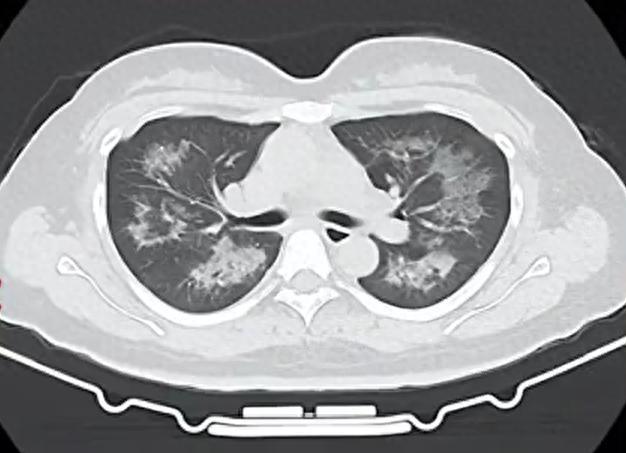

据先容,小江就诊时高烧朝上40℃,血惯例查验走漏白细胞、中性粒细胞、CRP(C-反映卵白)均昭彰升高,嗜酸性粒细胞也显贵偏高。

胸部CT进一步走漏,她的双肺出现多发斑片状恶浊影,被会诊为间质性肺炎。大夫判断,病因很可能与她近期恒久搏斗的某类物资相关。经过反复精细地揣测病史,小江才说出我方恒久、平时使用定妆喷雾的民风。